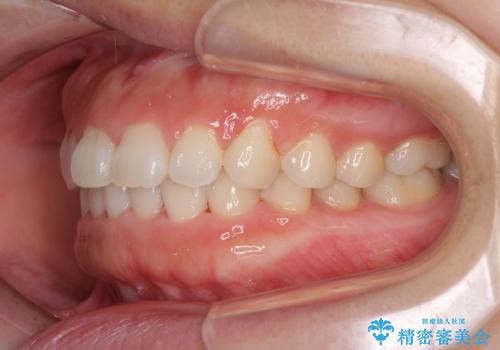

- 前歯のデコボコを治したいとのことで来院された患者様です。

上下顎ともに歯列全体の側方拡大とIPR(歯と歯の間を削る)によってデコボコが解消するように設計し、インビザラインにより治療を行うこととしました。

後方移動に際し、残っていた上顎の親知らずを抜歯することとしました。

1日22時間の装着時間をしっかり守ってくださったので、1年程度で治療を終えることができました。

1セットのマウスピースで概ね治療を終えたのですが、前歯僅かな叢生が残ったため、2セット目のマウスピースで仕上げました。

気にしていた口元の印象が改善され、患者様には大変満足していただきました。